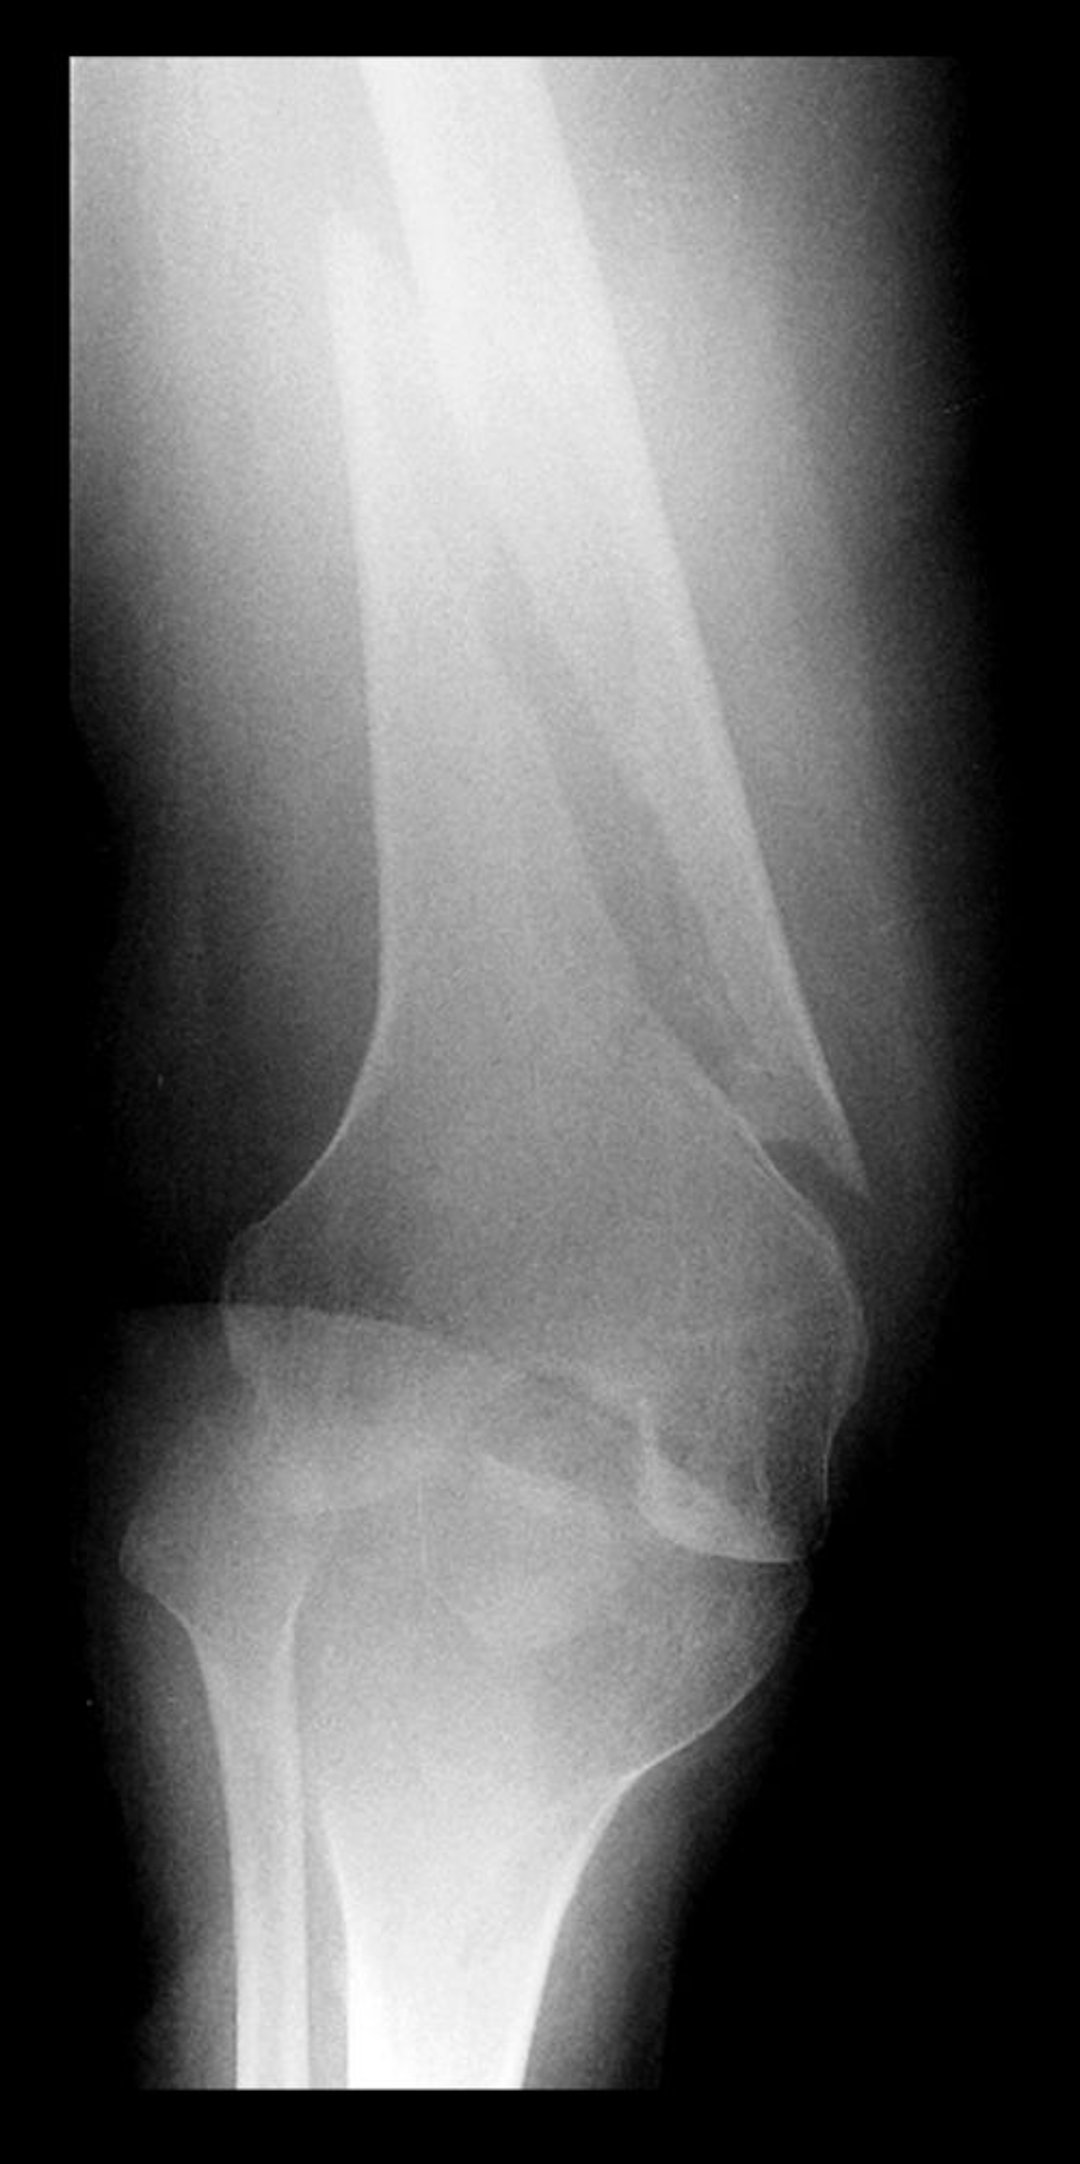

Diversi tipi di fratture

Frattura trasversale della diafisi della tibia

Questa frattura trasversale colpisce la parte mediale della diafisi della tibia.

Image courtesy of Danielle Campagne, MD.